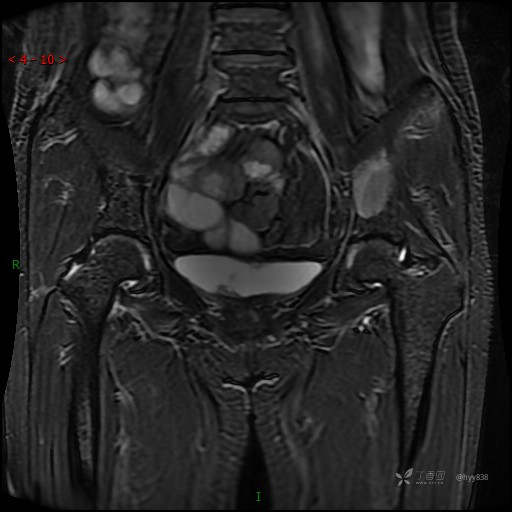

MRI T1WI+T2WI axi

Cor T1WI T2WI -fs